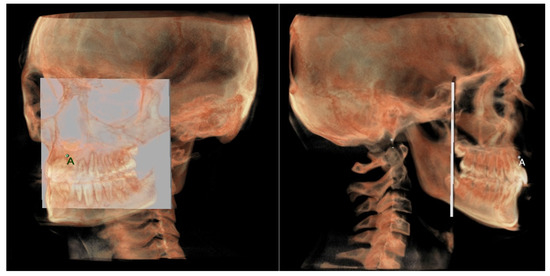

- The maxillary skeletal arch (Figure 6) was measured from point A to a plane passing through the PNS and parallel to the coronal plane.

- The maxillary dento-alveolar arch (Figure 8) was measured from the point SPr to a plane passing through the PNS and parallel to the coronal plane.